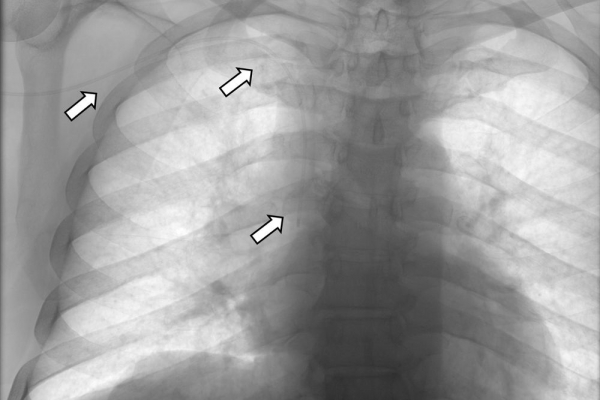

- Οι περιφερικά εισερχόμενοι κεντρικοί καθετήρες (PICC lines) είναι ειδικοί καθετήρες, οι οποίοι εισάγονται από μια περιφερική φλέβα συνήθως των άνω άκρων(π.χ βασιλική ή κεφαλική φλέβα) και προωθούνται μέχρι κεντρικής φλέβας πλησίον της καρδιάς (συνήθως στην άνω κοίλη φλέβα) ώστε να επιτευχθεί η ενδοφλέβια πρόσβαση. Οι καθετήρες PICC μπορούν να χρησιμοποιηθούν για την χορήγηση μιας ποικιλίας φαρμακευτικών θεραπειών ειδικά στον ογκολογικό ασθενή όπως αντιβιοτικών, αναλγητικών, χημειοθεραπείας, παρενετερικής σίτισης ή και για απλή αιμοληψία σε ασθενείς που νοσηλεύονται επί μακρόν στην κλινική ή στην μονάδα εντατικής θεραπείας, καθώς και σε ασθενείς οι οποίοι επιστρέφουν στο σπίτι και επανεισάγονται στην κλινική μόνο για την προκαθορισμένη χημειοθεραπεία τους.